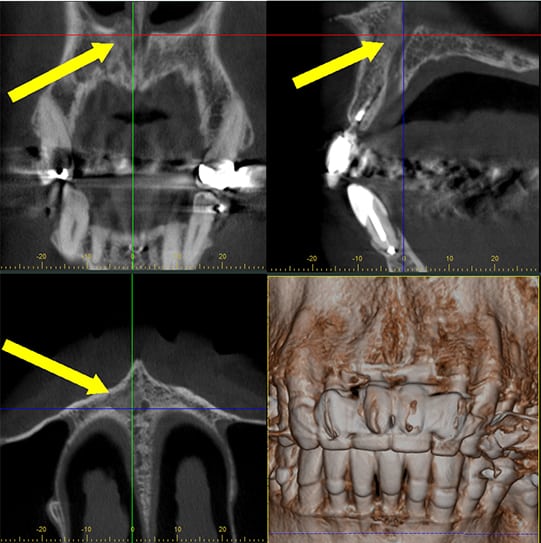

CBCT Interpretation

Cone beam computed tomography (CBCT) scans are prescribed mainly to assist in diagnosis-pre-surgical planning and to assess the results of certain types of treatments or periodic evaluations. The interpretation of a CBCT scan is a step-by-step analysis of all abnormal radiographic findings or features with the goal of recognizing and collecting as much information as possible that is available in the various image reconstructions.

Analysis of the collected information may lead the clinician to a diagnosis or, more frequently, to a short list of possible diagnoses.